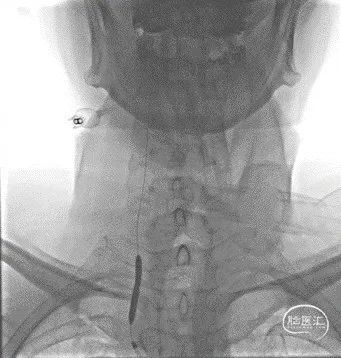

脑血管造影:主动脉弓+右侧颈总动脉造影。

左侧颈总动脉造影。

左侧锁骨下动脉造影。

右侧锁骨下动脉造影。